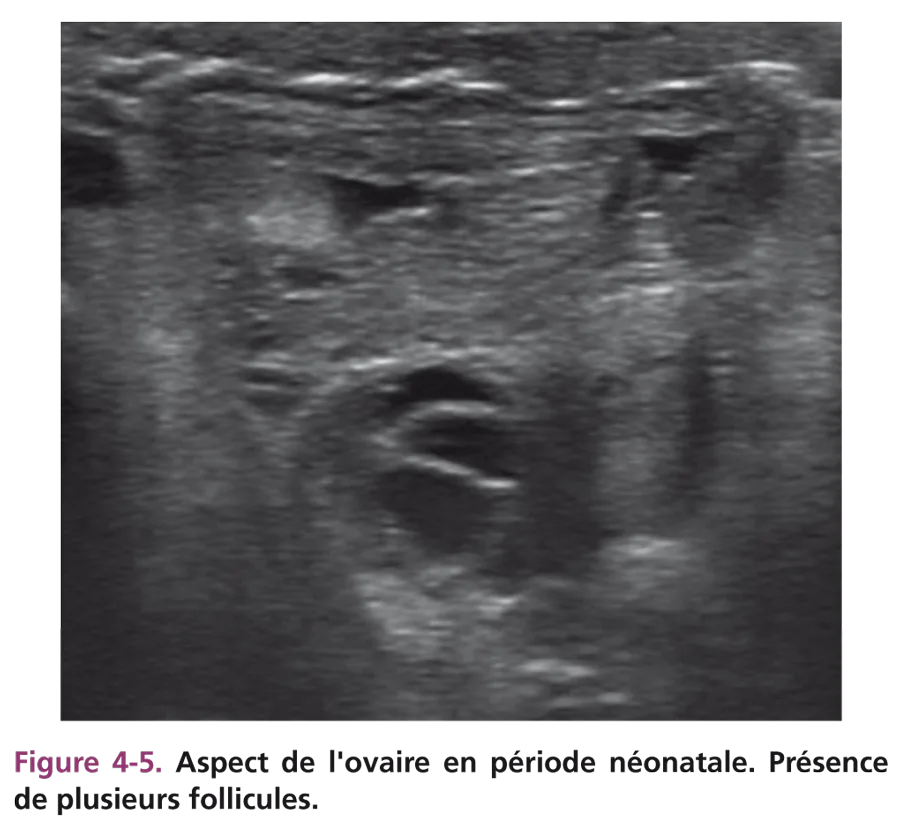

Les critères du développement ovarien tenant compte de la taille et de l’échostructure de l’ovaire sont plus difficiles à définir. Rappelons la difficulté à visualiser l’ovaire, souvent haut situé dans le pelvis, nécessitant une bonne réplétion vésicale. Si l’utérus est latérodévié, l’ovaire du même côté est difficilement perçu. Il peut être en position sus- ou rétroutérine (fig. 4-4). À la période néonatale, la taille de l’ovaire est fonction du développement folliculaire lié à la stimulation hormonale gonadotrope maternelle. Plusieurs follicules (taille supérieure à 5 mm) sont visibles, hypo- ou anéchogènes (fig. 4-5). Comme pour l’utérus, cet aspect est transitoire. Les kystes folliculaires (diamètre supérieur à 20 mm) sont fréquents pendant la grossesse et à la période néonatale.

Fig 4-5